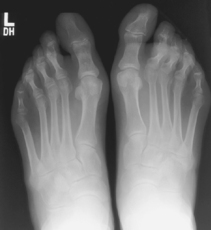

Lateral projection is most common for longitudinal arch (flat feet), AP demonstrates alignment of metatarsals and phalanges.